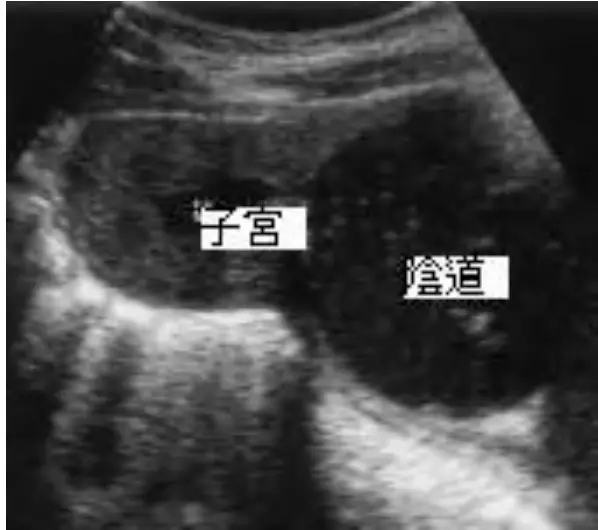

15歲女性,第二性徵發育正常,但未有初經並有週期性腹痛,超音波如圖所示,下列處置何者最不適當?

影像分析:

超音波可見子宮前方呈中等回聲的實質構造,後方緊鄰一個邊界清楚、內含無回聲液體的大囊性腔室,標示為「陰道」。該腔室明顯擴張,符合大量積血(hematocolpos)或合併 hematometra 影像。子宮壁與內膜層結構完整,排除子宮缺如或發育不全。整體圖像典型指向 hymenal 或陰道遠端阻塞所致的經血滯留。(pubmed.ncbi.nlm.nih.gov)